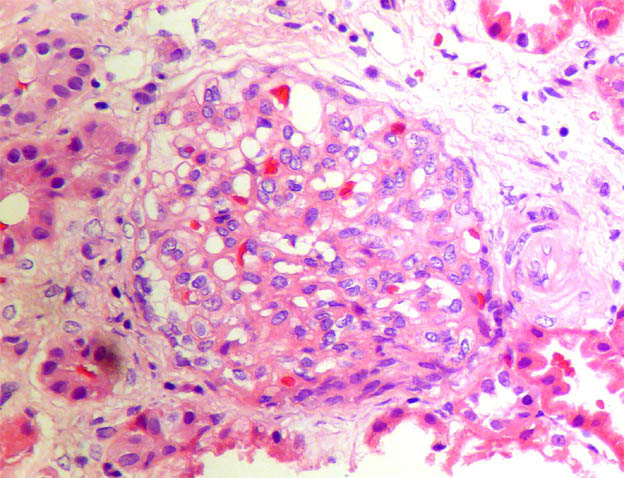

The patient is a 11-year-old boy with a history of steroid-resistant nephrotic syndrome since he was 7 years old. Renal biopsy at 8 years was diagnosed as focal segmental glomerulosclerosis (in another center, we do not have histological images). He continues with nephrotic syndrome since and now the serum creatinine has increased: 1.4 mg/dL. A new renal biopsy is undertaken to see the severity of the histological changes and decide whether to try another immunosuppressant treatment.

See the images of the second renal biopsy.

Figure 2. H&E, X200.